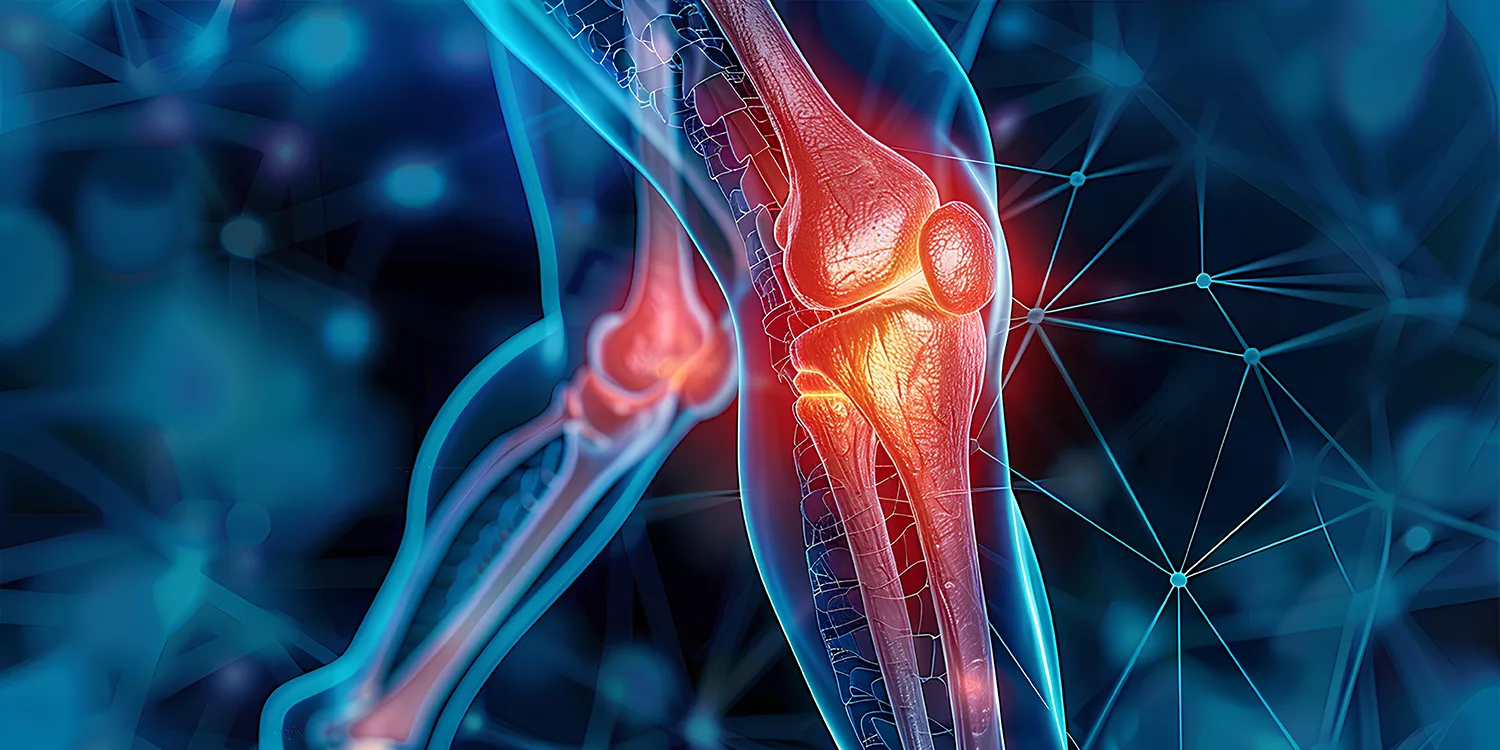

Joint Replacement Surgery

Our specialists perform hip, knee, and shoulder replacements using minimally invasive techniques. These advanced procedures result in shorter recovery times, less pain, and faster rehabilitation. We’re known as the best hospital for orthopaedic surgery in the area, with a proven record of success in joint replacement and restoration.

Robotic-Assisted Joint Replacement

As a leader in joint replacement surgeries, we offer robotic-assisted options. This advanced technology enables high precision, shorter recovery times, and better postoperative outcomes.

- Knee Replacement Surgery

- Hip Replacement Surgery

When is joint replacement surgery needed?

If arthritis or joint damage severely affects mobility and pain management fails, joint replacement may be recommended.